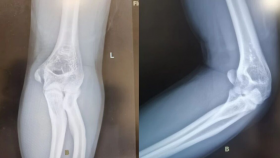

近日,我院小儿骨科联合运动医学科为一位12岁的胫骨平台骨折女童完成关节镜下手术。患儿入院后,小儿骨科医生为其完善了检查,发现患儿为左膝胫骨平台骨折,CT显示其胫骨平台塌陷0.5cm。儿童胫骨平台骨折比较罕见,治疗起来也比较棘手。因患儿年幼,骨骼发育尚未成熟,胫骨近端骨骺骺板未闭合,不适当的治疗可能会加重骨骺的损伤,影响患儿膝关节发育,同时,骨折累及胫骨关节面,打开膝关节直视下复位,又会造成关节内较大的损伤和皮肤瘢痕。经全科讨论,决定联合运动医学科发挥关节镜的优势,在关节镜下进行骨折闭合复位内固定微创手术治疗。经过充分术前准备,运动医学科主任葛兴涛和小儿骨科主任许洪涛联合实施了手术。术中,葛兴涛对患儿进行了关节镜检查,排除了关节内的其他损伤,直视下观察到关节面塌陷的情